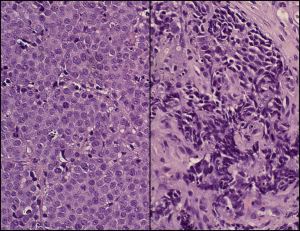

They took normal human prostate cells from healthy donors and added the MYCN gene which then produced large amounts of N-Myc protein. After receiving an N-Myc boost, the normal basal cells developed into aggressive tumor cells. When these transformed cells were transplanted into mice, they generated NEPC tumors.

Further experiments revealed that N-Myc was required for maintaining the deadly nature of the NEPC tumors. If N-Myc expression was disrupted, then the tumors in the mice actually shrank. After establishing N-Myc as a therapeutic target, they went on a hunt for drugs that could block its tumor amplifying activity.

They tested a drug that originally was designed to treat childhood brain cancers that also had an N-Myc related cause. The drug, CD532, acts on a protein called Aurora A kinase. The kinase physically interacts with N-Myc and is required to keep N-Myc stable and able to do its job. When mice with NEPC tumors were treated with CD532, the effects were dramatic – their tumors shrank by as much as 80%.